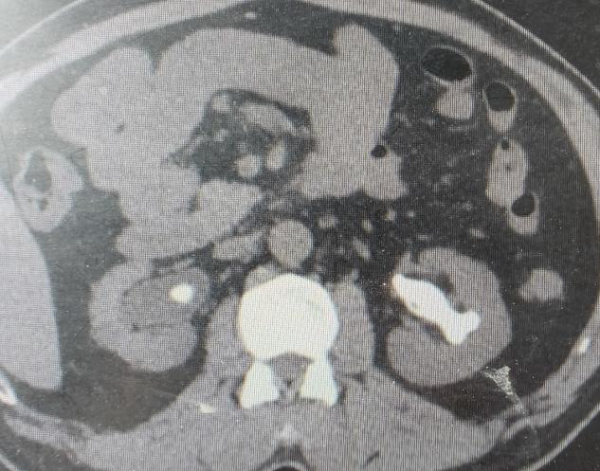

许多年前的一次体检,朱先生得知自己患有双肾结石。因当时症状不明显,也未规律复查。时间一晃而过。近期,朱先生时常感到腰部隐隐酸胀,体力也大不如前。他原以为是年纪大了的正常现象,直到一次剧烈的腰痛发作,才在家人的催促下就医,检查结果让他和家人都大吃一惊。CT显示,他的双肾结石,其中左肾几乎填满了各个肾盏,合并积水及感染,并且明确糖尿病,血糖超高。

“就像一个模具里灌满了石膏,结石完全依照肾脏内部的空腔形状生长,处理起来非常棘手。”泌尿外科主任、副主任医师刘伟光介绍,“尤其朱先生还有糖尿病,这大大增加了手术的复杂性和感染风险。”

术后复查影像显示,朱先生的双侧肾脏结石已完全取净,肾积水消失。困扰朱先生多年的“石头包袱”,终于被彻底卸下。